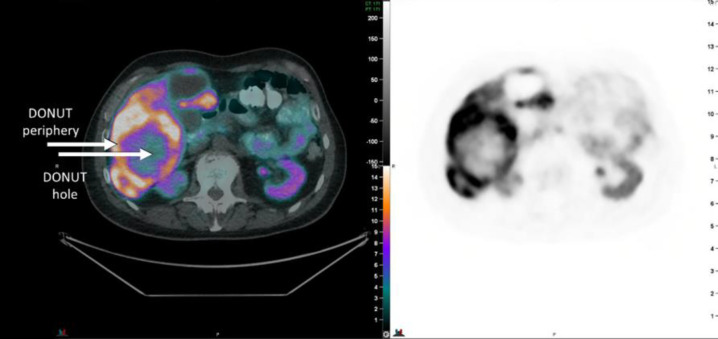

Objectives: The phenomenon of peripheral [68Ga]DOTATATE avidity without central avidity (which we have termed a "DONUT") has been observed in neuroendocrine neoplasm (NEN) lesions. There has been speculation as to whether this is due to hypoxia, de-differentiated disease or other causes. The presence of hypoxia may have prognostic and therapeutic implications, and was evaluated in these lesions using the PET hypoxia imaging biomarker [18F]FMISO.

Methods: Prospective pilot study in patients with metastatic NENs with at least one DONUT lesion (central [68Ga]DOTATATE non-avidity). [18F]FDG and [18F]FMISO scans were acquired within 60 days of the [68Ga]DOTATATE PET/CT. [18F]FMISO scans were acquired as a dynamic scan over 20 mins from injection with a delayed image at 2 hours. The dynamic acquisition was analysed quantitatively using a graphical approach yielding parametric images of Influx Rate Constant and Volume of Distribution. [18F]FMISO uptake within the identified DONUT hole on the 2 hr delayed scan was qualitatively scored by two experienced nuclear medicine physicians as: 0 (no uptake), 1 (uptake less than normal liver), 2 (uptake equal to normal liver), or 3 (uptake greater than normal liver).